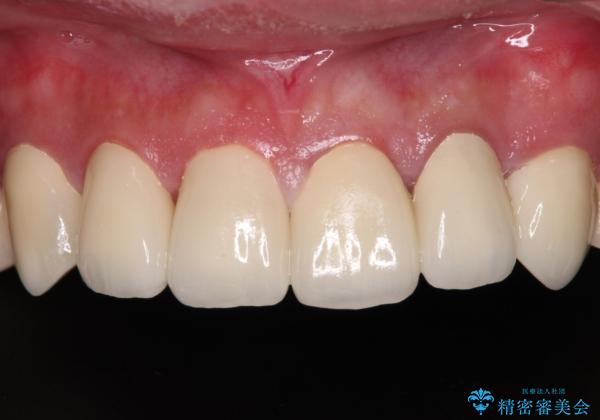

- むし歯の影響で、前歯を見せることが恥ずかしいとのことで来院された患者様です。

全顎的にむし歯が多く、治療が必要な歯はたくさんありましたが、まずは非常に目立つ前歯から処置を行うこととしました。

むし歯は歯肉内にまで進行していると外科処置が必要となりますが、ギリギリの位置でとどまっていたため、速やかにオールセラミッククラウンにて補綴治療することとしました。

むし歯は多かったものの、歯肉の腫脹はそれほどなかったため、最小限の治療回数で治療を終えることができました。